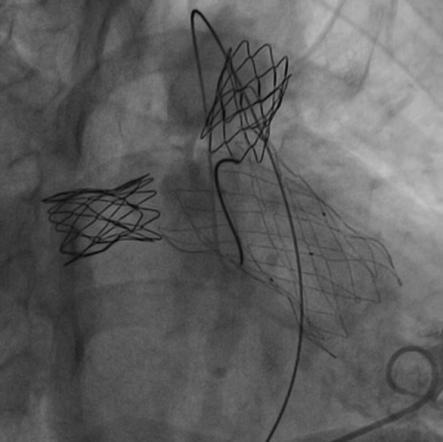

患者在全麻下,首先从左股静脉将造影导管分别送至右心室和肺动脉主干,行造影以明确右室流出道、肺动脉及肺动脉分支的基本情况。同时测量了右室流出道及肺动脉的尺寸。随后输送器通过右侧股静脉延加硬导丝将瓣膜输送到右室流出道,在X线的引导下,将瓣膜精确定位到植入部位并顺利进行瓣膜释放,无反流和瓣周漏,手术效果十分理想。

高主任总结道:本例病例就是在没出现严重肺动脉反流时,先解决了严重的左右肺动脉分支起始部狭窄,不仅促使狭窄远端肺血管的发育,避免了肺动脉分支的闭塞。随着年龄长大,肺动脉反流加剧,右心功能受损时,我们及时植入肺动脉带瓣支架,阻滞了右心功能向失代偿期的发展。

随着介入技术和介入材料的改进,通过经皮介入技术可以替代传统的外科手术。特别是肺动脉支架和肺动脉带瓣支架的应用,替代传统外科手术,可以起到非常好的效果。这2类支架,在同时出现狭窄和肺动脉严重反流时可以同时应用。一次性解决肺动脉分支狭窄和肺动脉反流问题。如果只有肺动脉分支狭窄,反流并不严重时,可以先处理肺动脉分支狭窄,也就是可以在狭窄部位植入Pul-Stent®肺动脉支架进行扩张。一旦解除了狭窄,也会延缓肺动脉反流的加剧。这样可以保护了右心功能,促使肺血管发育,而且会推迟肺动脉反流干预的时间。